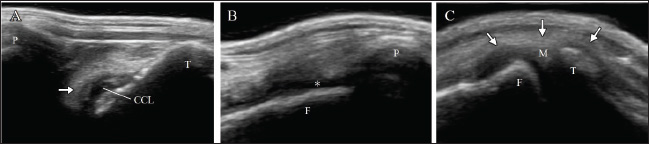

Radiography of the right stifle joint indicated infrapatellar fat pad signs and cranial tibial luxation (Fig. 1A). No obvious angular limb deformities were observed (Fig. 1A and D). Ultrasonography of the stifle joints (ARIETTA Prologue; Fujifilm Co., Japan; 18 MHz linear probe) revealed a complete CCLR, severe joint effusion, and medial buttress in the right stifle joint with no injury to the medial meniscus (Fig. 2A–C). Furthermore, partial CCLR and mild joint effusion were observed in the left stifle joint.

Fig. 2. Ultrasonography of the right stifle joint at the first visit. Complete rupture of the cranial cruciate ligament (arrow, A) and severe joint effusion (asterisk, B) can be observed. Although the medial buttress (arrow, C) can be visualized, the caudal horn of medial meniscus shows no damages (C). CCL=cranial cruciate ligament; F=femur; M=medial meniscus; P=patella; T=tibia.

Left weight-bearing lameness with pain upon hyperextension and swelling in the left stifle joint were reported 8 weeks post-surgery of the right limb. The results of the cranial drawer and tibial compression tests performed as a part of the orthopedic examination of the left limb were positive. Radiography revealed the presence of the infrapatellar fat pad sign and cranial tibial luxation at the left stifle joint, with no obvious angular limb deformities (Fig. 4A and D). Ultrasonography of the left stifle joint revealed complete CCLR, moderate joint effusion, and medial buttress without damage to the caudal horn of the medial meniscus (Fig. 5A–C). Preoperative radiographs revealed a TPA of 25°. A 2.4-mm TPLO plate (VP4404-L3; DePuy Synthes Japan, Japan) was selected for TPLO. Identical to the measurements for the right limb, D1 and D2 for the left limb were 7.5 and 8.2 mm, respectively.

Fig. 5. Ultrasonography of the left stifle joint at 8 weeks after surgery on the right limb. The joint shows complete rupture of cranial cruciate ligament (arrow, A), moderate joint effusion (asterisk, B), and the medial buttress (arrow, C). The caudal horn of medial meniscus shows no injury (C). CCL=cranial cruciate ligament; F=femur; M=medial meniscus; P=patella, T=tibia.